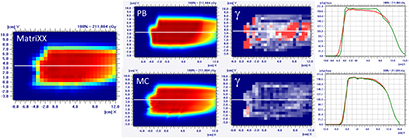

Figure 8 presents the plan optimized and calculated with the PB algorithm for the brain target of the lamb's head with a gantry angle of 0° and the RS 30 cm from the isocenter. MC recalculation shows significant differences in the dose volume histogram (DVH) and mostly located in the distal part of the target.

Figure 8. PB optimized dose distribution on the brain target of the lamb head (top left) and MC recalculation (middle left) with a proton field angle of 0° and the RS 30 cm from the isocenter (i.e. air gap ~20 cm). The white lines represent the dose profiles' (bottom) extraction plans. On the right side of the figure, the DVHs of both dose distributions (top right) and dose difference (middle right) are displayed.

Standard image High-resolution imageFrom the MatriXX measurements, it is clear that the PB algorithm over-estimates the target coverage (figure 9) and also in the case of small air gaps (i.e. RS 18 cm from the isocenter) the PB γ passing rate is <90%; the splitting technique improves the agreement between the measurements and the calculation performed with the PB dose engine (table 3).

Figure 9. Dose distribution and γ analysis comparison between the MatriXX measurement and the PB or MC dose engine in a transversal plane for a lamb's head, brain target, with a gantry angle of 0° and the snout position at 30 cm. The white lines represent the dose profiles' extraction plans, the red lines are the measured data profile while the green lines represent the calculated dose distribution. The red region in the γ graph represents the area with γ > 1.